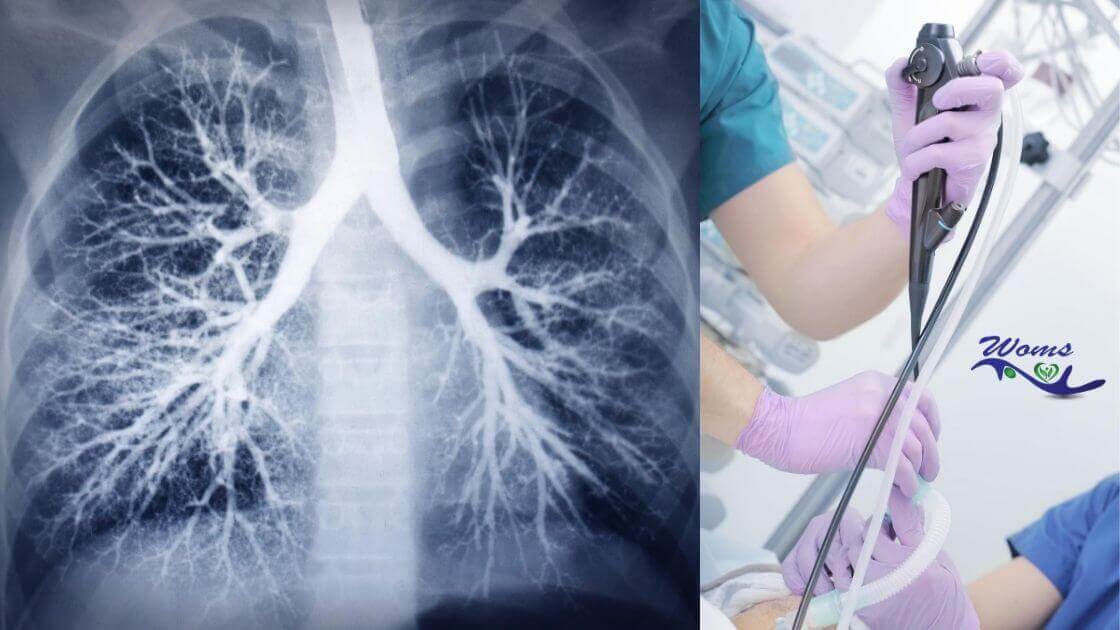

What is pulmonary toilet?

The pulmonary toilet was a term used initially used but now instead of it, pulmonary hygiene is used. Pulmonary bronchial hygiene is also called chest physiotherapy. So, you might be confused by hearing the name pulmonary toilet. You may have questions like what does it mean and why it is important and other following questions too. So let’s know about it more.

Pulmonary hygiene is some exercise and procedure which is used to clear our airways of mucus and other secretions. It helps to provide sufficient oxygen to the lungs and also ensures whether our respiratory system is working well or not.